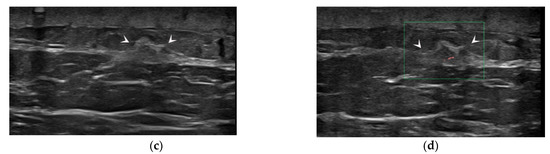

The Usefulness of Magnetic Resonance Imaging (MRI) for the Detection of Local Recurrence after Mastectomy with Reconstructive Surgery in Breast Cancer Patients